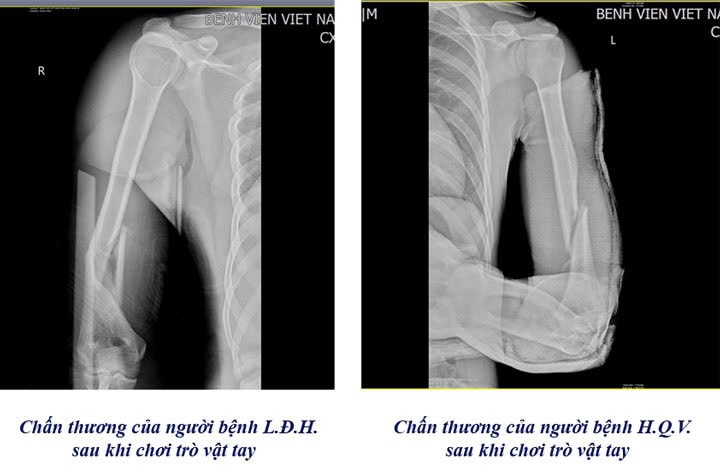

Hình ảnh X-quang cho thấy vị trí gãy xương cánh tay của bệnh nhân. Ảnh: BVCC

Theo các bác sĩ Khoa Chấn thương Chỉnh hình & Bỏng, khi vật tay, lực xoay đột ngột tác động lên xương cánh tay có thể vượt ngưỡng chịu đựng, gây gãy xoắn xương cánh tay, thậm chí di lệch.

Những trường hợp này thường cần phẫu thuật kết hợp xương bằng nẹp vít - kỹ thuật phổ biến, mang lại hiệu quả cao, giúp cố định vững chắc vị trí gãy và hỗ trợ quá trình liền xương.